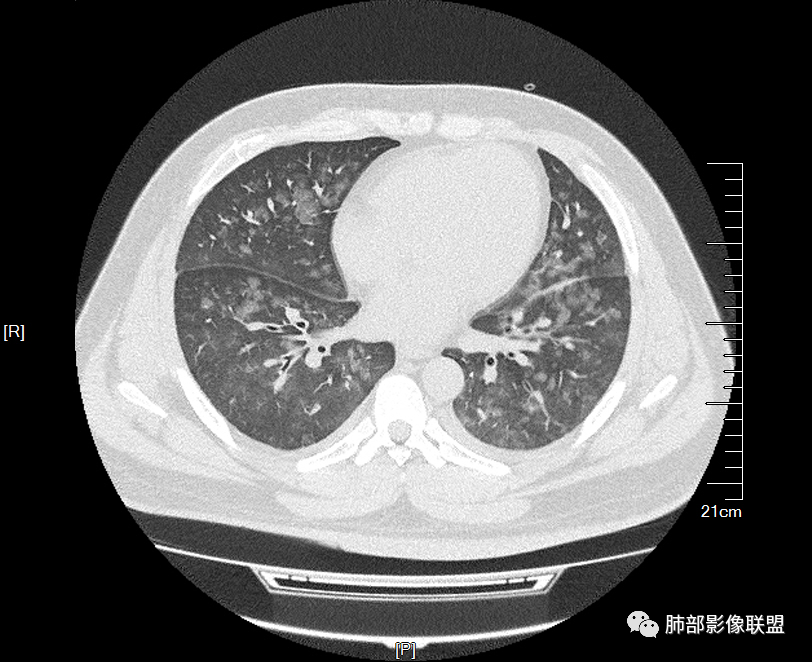

多发GGO结节,边界清,以全小叶、小叶中心为主:

GGO背景

小叶间隔增厚,无明显重力趋势

中轴间质稍增厚

细网格也明显

中轴间质增厚,小叶间隔增厚,小叶内间质增厚,部分重力作用,双侧对称,胸水,按理淋巴道回流受阻有

肺水肿类病变有

问题是腺泡结节如何解释?

一般吸入性病变,肺泡腔充填性病变

时间的问题,,为什么呢,就是说,我们一般就是这样,假如这些急性的单纯的非常超急性的,那就是说,肺泡腔充填的,明显的小叶间隔增厚,那我们警惕,不对,这个是不是间质为主的,以小叶为单位间质为主的病变。

一开始怀疑吸入的病变,但我看了一下很多全小叶性的,确实小叶核心区域,稍微密度偏高一点那种,我认为就是稍微一点吸收阶段都是那样的,这个我觉得还是肺泡腔充盈为主的病变,不太符合一个吸入的改变。